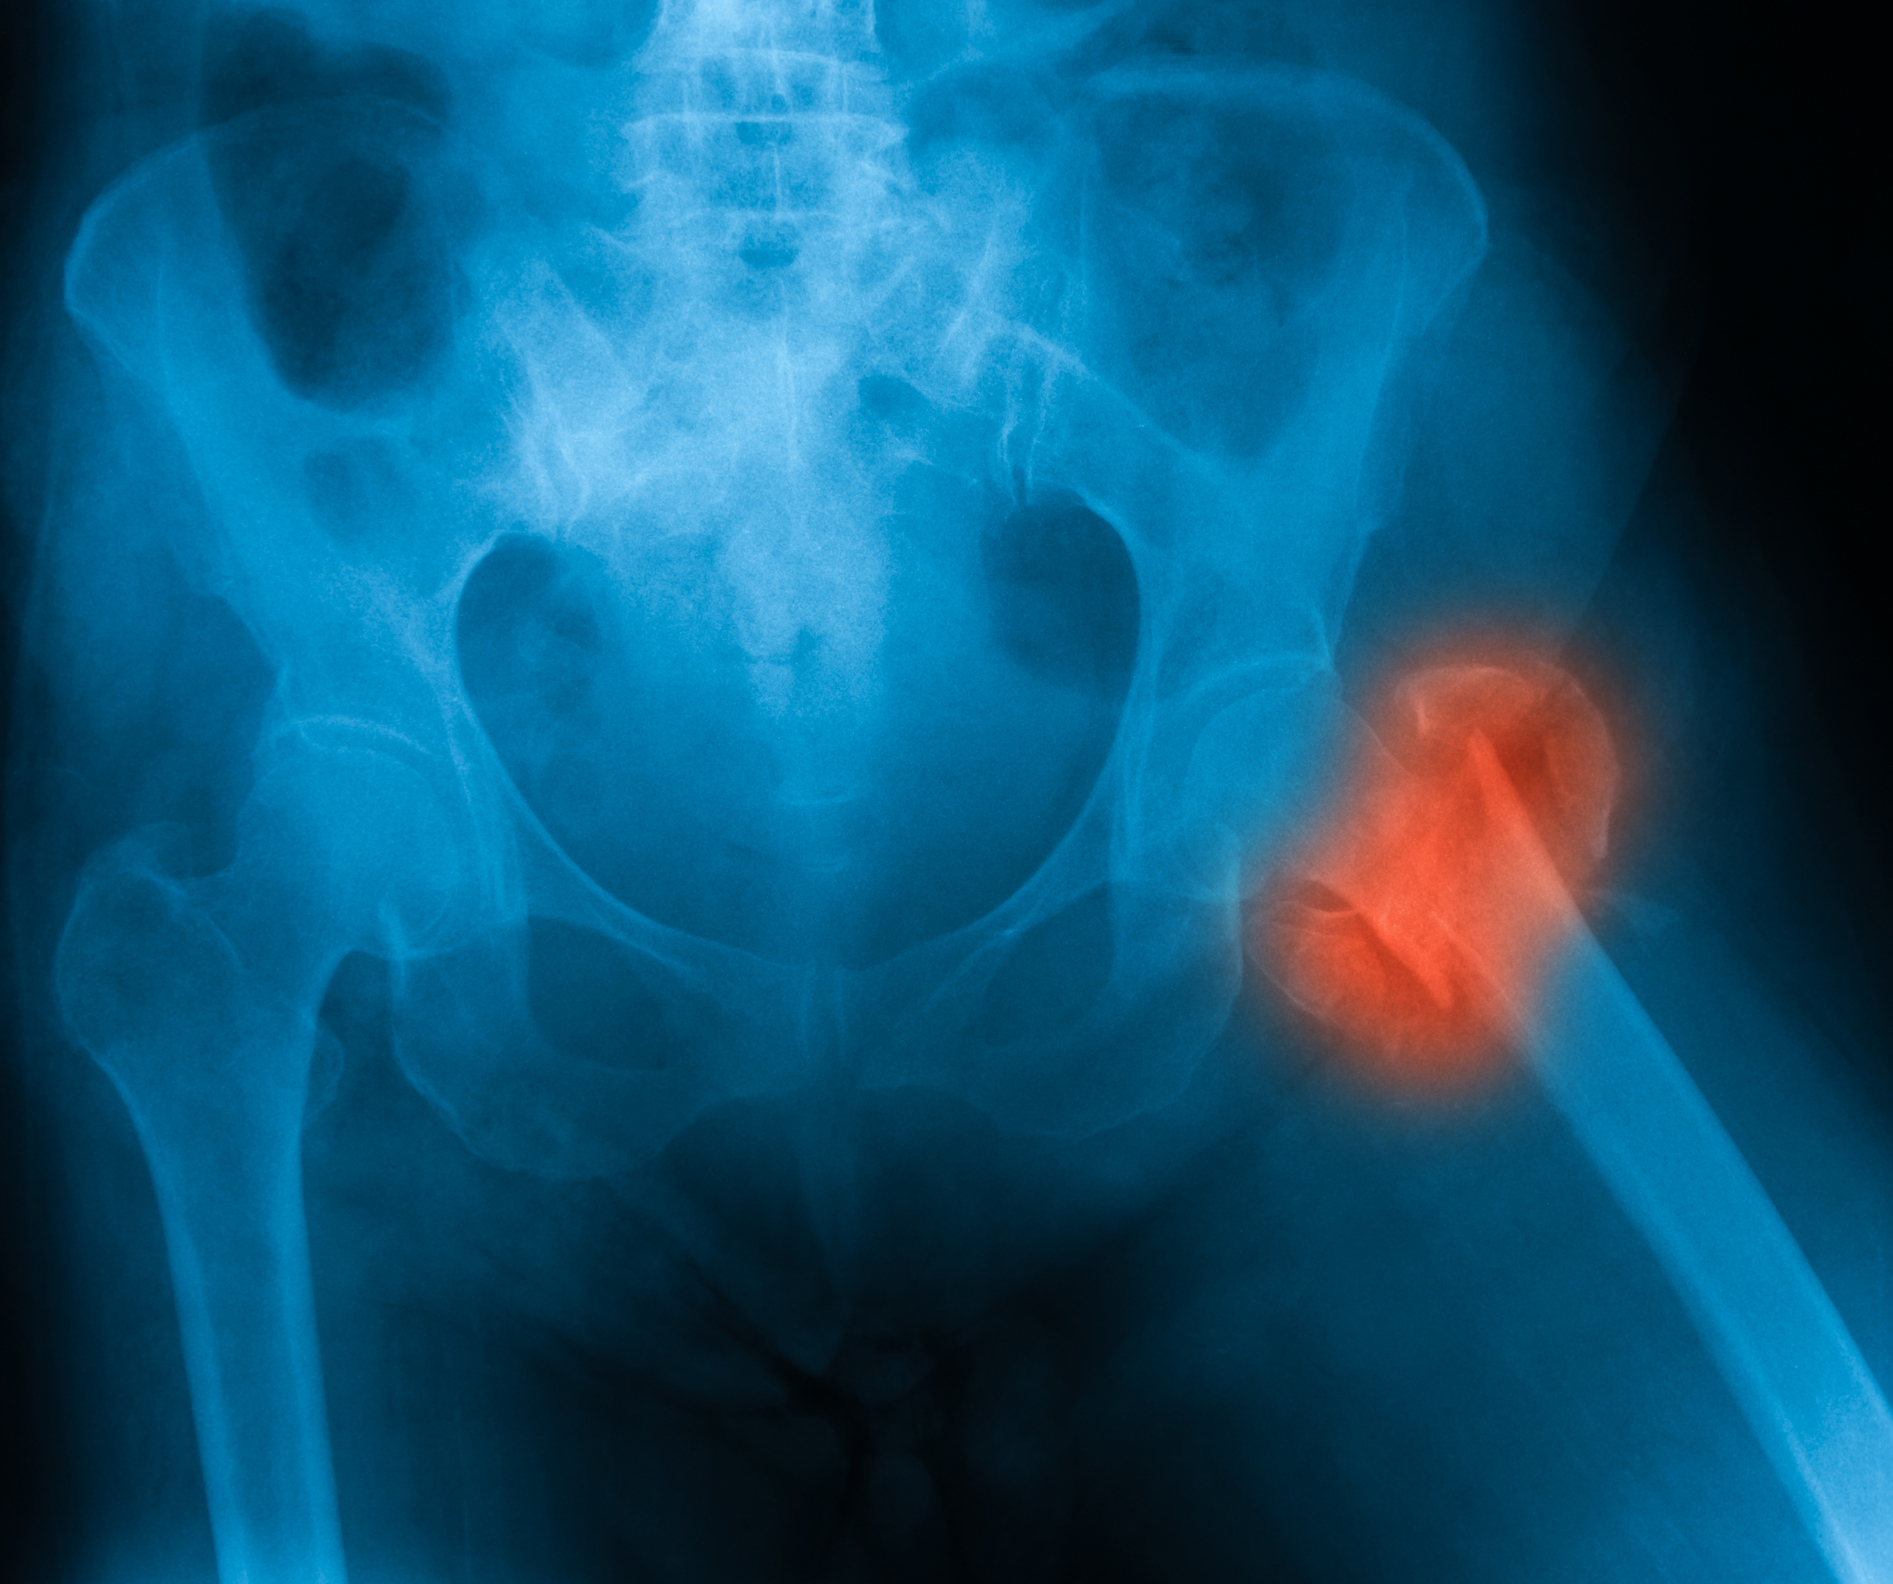

Osteoporosis risk increases in seniors suffering from hip fracture: New study

Every year, at least 250,000 people are hospitalized for hip fractures, yet many don’t realize the injury is associated with osteoporosis risk. New research suggests that seven out of 10 older adults who experience hip fractures are not told they could have osteoporosis. Osteoporosis is a condition in which the bones become brittle and fragile ...click here to read more